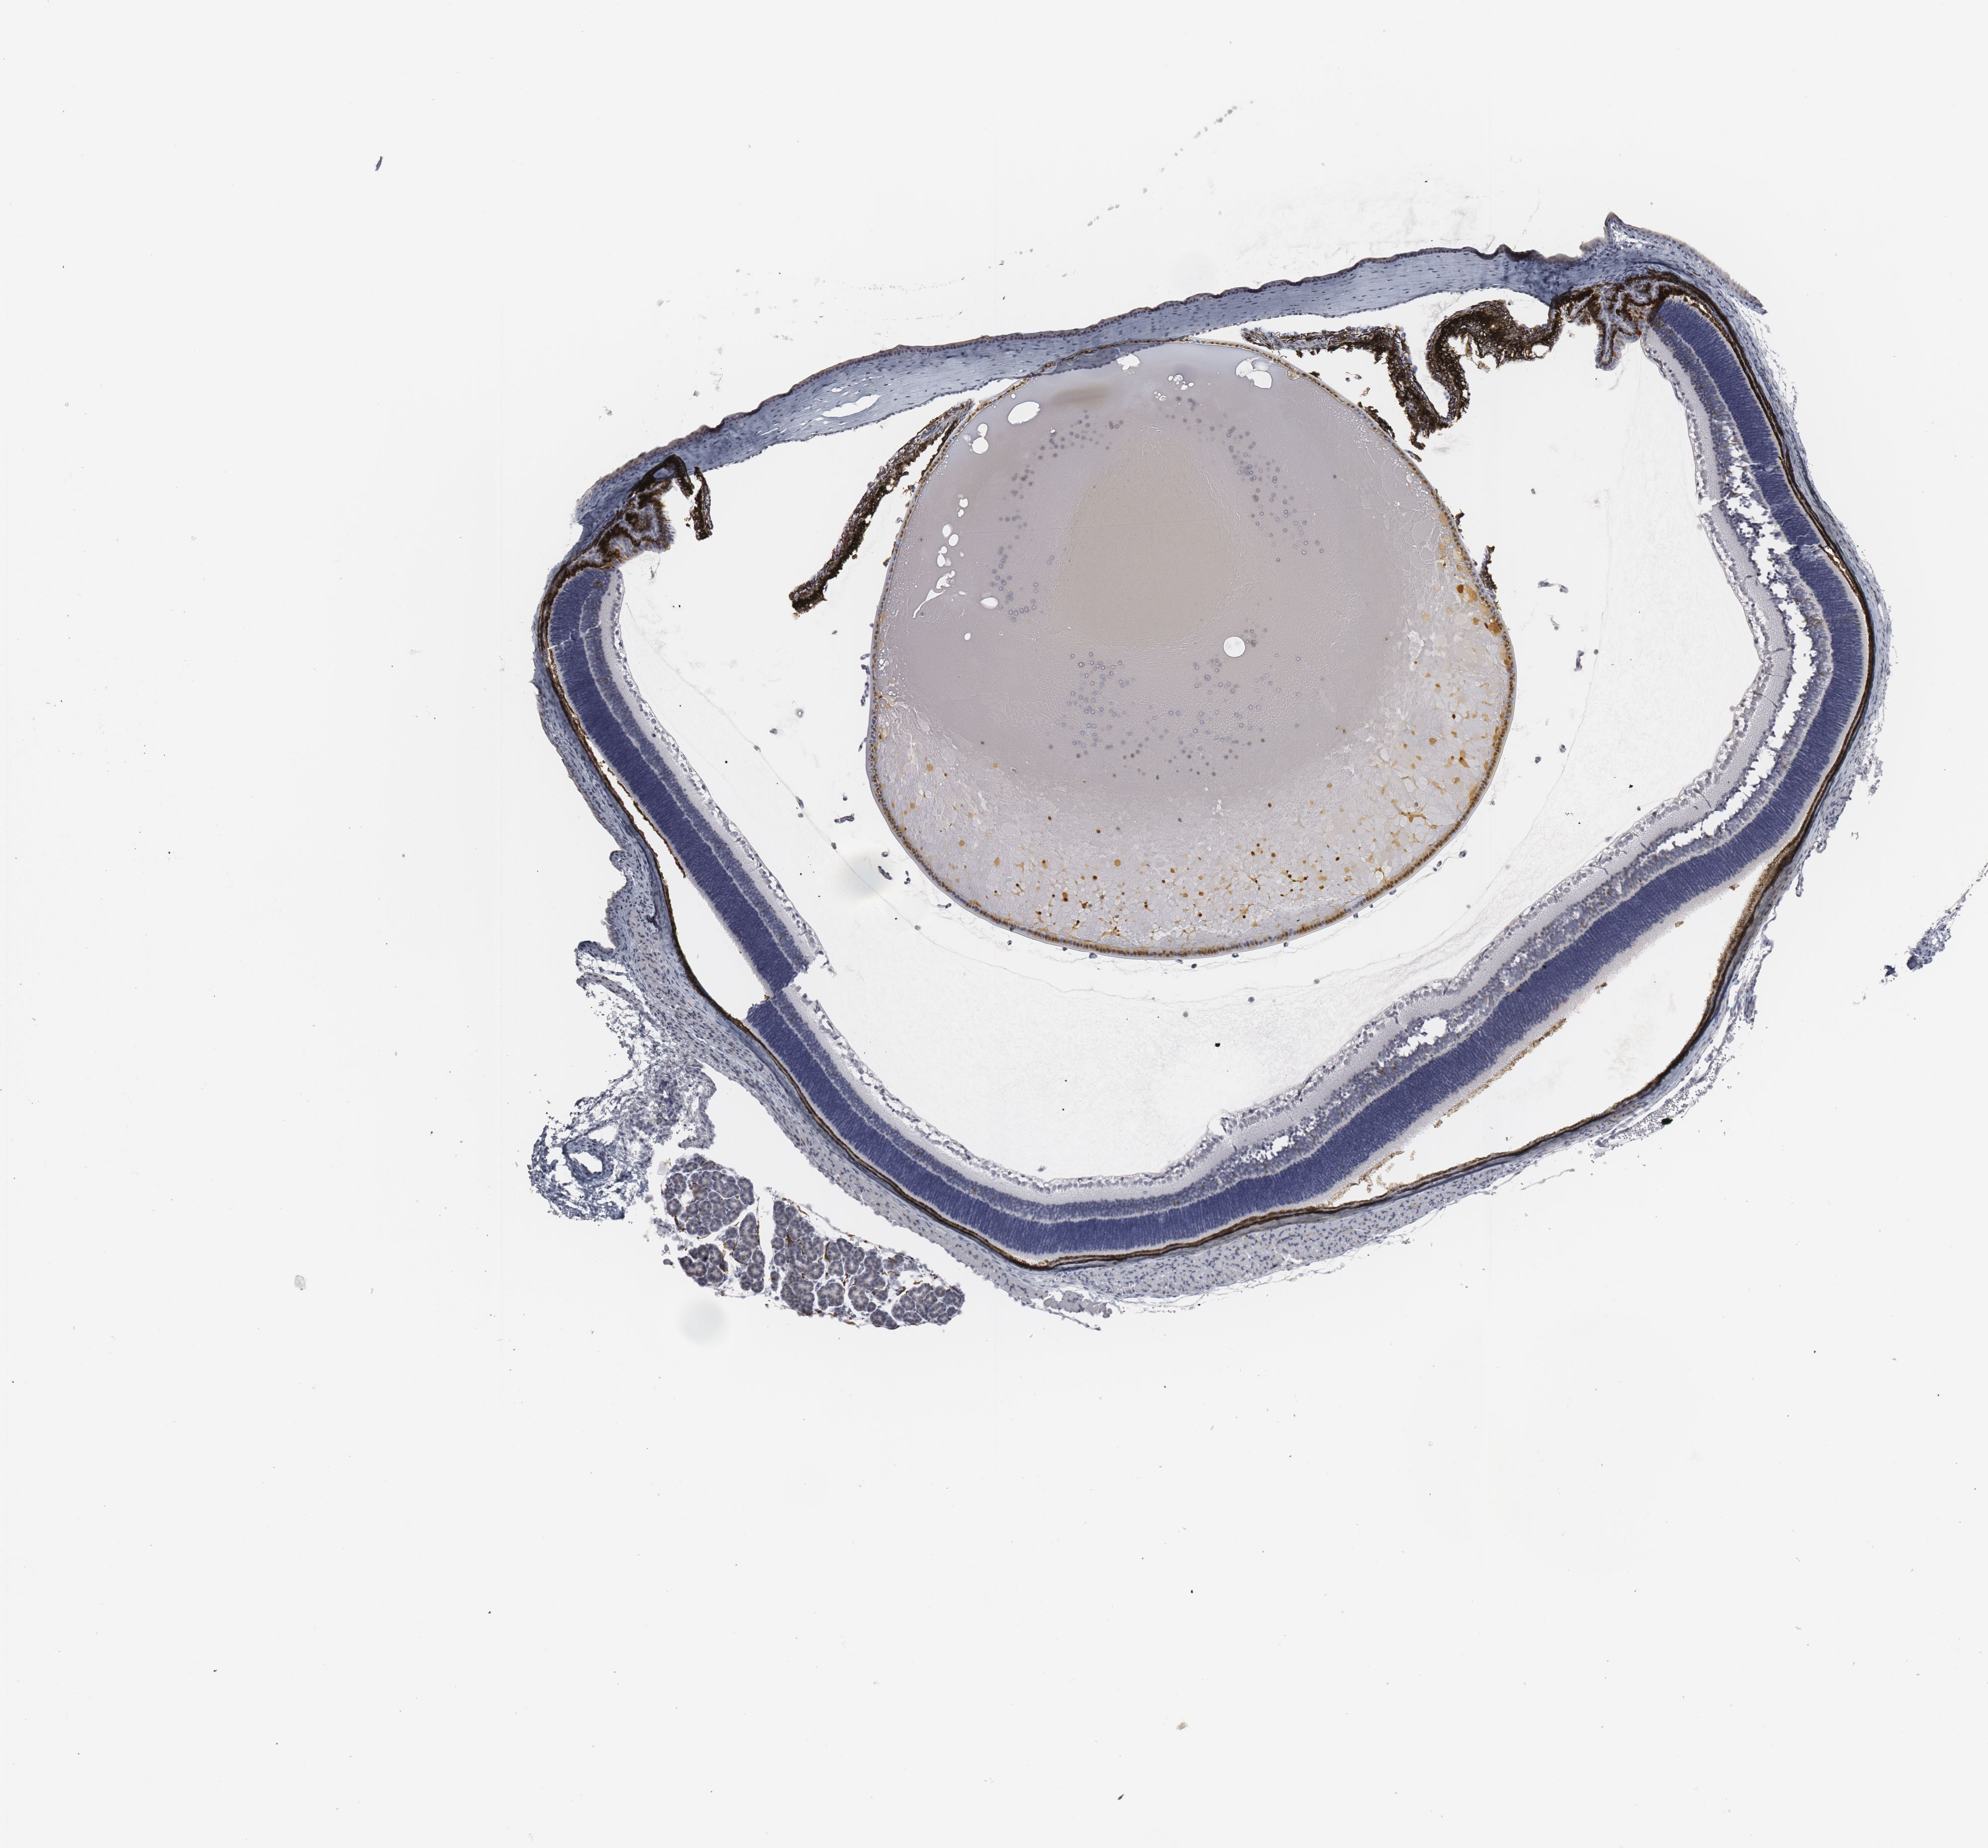

FLAG: Immunoperoxidase staining of formalin fixed, paraffin embedded, Flag-tagged mouse eye showing nuclear staining.